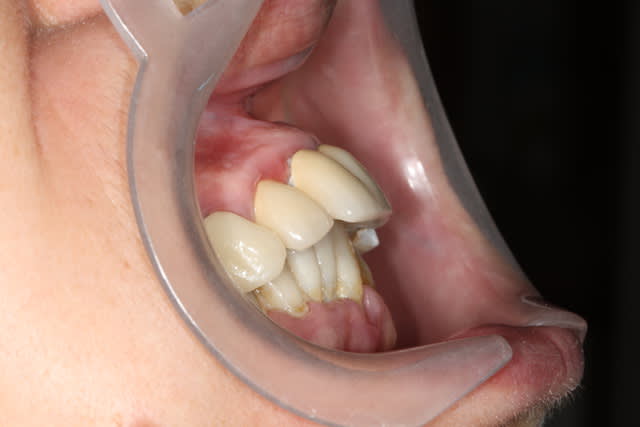

Je vous présente un cas que je viens de finir , il n'était prêt pour l'ADF . C'est un cas complet où j'ai pu exprimer mon art dans tous les domaines , endo , paro , ortho , prothèse .

Bon je réponds donc à l'élongation coronaire de la 32 . Cela m'a semblé nécessaire après le traitement ortho de la 11 , l'équilibration est à la fois diagonalement réussie et très harmonieuse . Il ne s'agit donc pas d'un surttt , d'ailleurs ce n'était pas dans le devis et il n'y eut pas de surcoût pour la patiente .